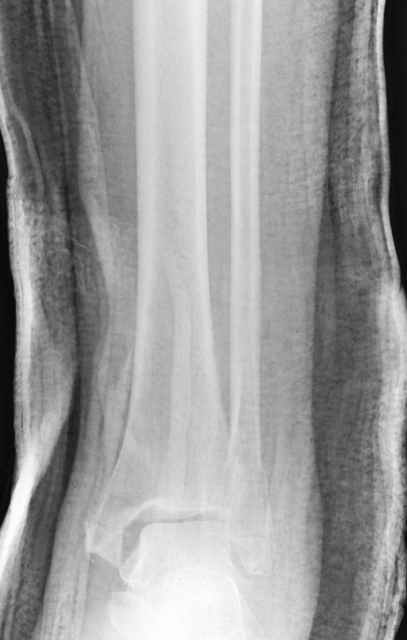

Еще, кстати, о фиксации лодыжки, если уж непременно хочется ее отдельно стабилизировать - при таком характере перелома замечательно должен сработать предложенный проф. Лазаревым с соратниками способ фиксации напряженной V-образной спицей. Опять же, открытая репозиция не нужна, мы делаем непрямую репозицию именно аппаратом. В приложении пример, там перелом малоберцовой куда менее поперечный, чем в данном случае, но все равно получилось закрыто без пластинки.

A propos fibular fixation if one is eager to stabilize it separately. In the fracture pattern a way of closed fixation by V-shaped stressed wire (advanced by colleagues from Moscow, prof. Lazarev A.F. et al.) must be excellent. We use indirect closed reduction by the external fixator. Example attached, that fibular fracture is even more suitable for plating but the wire did the job.

Идея хорошая, особенно если короткий и поперечный перелом. Узнал о методе на прошлогодней конференции в Санкт Петербурге, доклад от ЦИТО,

и в доказательство Александр показал на своих снимках оригинальность метода, концепция "сделай сам имплант" из малого разреза и доступность. (при совершенствовании методики и инструментарии, метод может быть применен и в других случаях)